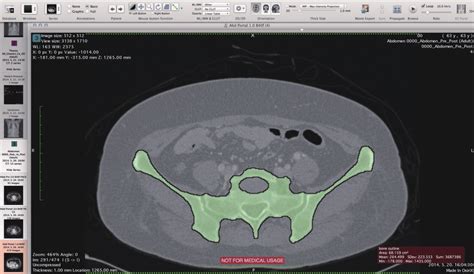

Osirix is an open-source DICOM viewer, and image processing software specifically designed for medical images. DICOM, which stands for Digital Imaging and Communications in Medicine, is the standard for handling, storing, printing, and transmitting information in medical imaging. Osirix is primarily used in the medical field by radiologists, surgeons, and other healthcare professionals to visualize and analyze medical images, such as those obtained from CT scans, MRI scans, PET scans, and ultrasound. This powerful tool offers a range of features, including 2D and 3D visualization, image reconstruction, and advanced analysis tools, making it an indispensable asset in modern medical diagnostics and treatment planning. Osirix distinguishes itself through its user-friendly interface, robust functionality, and the fact that it is open-source, allowing for continuous development and customization by a global community of users. Its capabilities extend to image registration, fusion, and segmentation, further enhancing its utility in complex clinical scenarios. Whether for routine diagnostics or advanced research, Osirix provides a comprehensive platform for medical image analysis, contributing significantly to improved patient care and outcomes. Radiologists and other medical professionals leverage Osirix to enhance their diagnostic accuracy and streamline their workflows. The software’s intuitive design allows for easy navigation and manipulation of complex datasets, enabling clinicians to quickly identify and assess critical anatomical structures and pathological conditions. Furthermore, the ability to customize Osirix through plugins and extensions means that healthcare providers can tailor the software to meet their specific needs and research interests. The open-source nature of Osirix also fosters collaboration and knowledge sharing among users, leading to continuous improvements and innovations in medical imaging analysis. In essence, Osirix embodies the principles of accessible, cutting-edge technology, empowering healthcare professionals to deliver the best possible care to their patients. With its widespread adoption and ongoing development, Osirix remains at the forefront of medical imaging software, shaping the future of diagnostics and treatment in healthcare systems worldwide.

In Indonesia, Osirix is gaining traction as a vital tool in hospitals, clinics, and research institutions. Its open-source nature makes it an attractive option for healthcare providers seeking cost-effective solutions without compromising on functionality. Indonesian radiologists and clinicians use Osirix for a variety of purposes, including visualizing CT scans, MRI scans, and other medical images to diagnose diseases, plan surgeries, and monitor treatment progress. The software’s advanced features, such as 3D reconstruction and image fusion, enable healthcare professionals to gain a comprehensive understanding of complex anatomical structures and pathological conditions. Moreover, Osirix’s compatibility with DICOM standards ensures seamless integration with existing imaging equipment and PACS (Picture Archiving and Communication System) networks, facilitating efficient workflow management. The adaptability of Osirix to different clinical settings and its ability to be customized through plugins make it a valuable asset for Indonesian healthcare providers. Training programs and workshops are being conducted to equip medical professionals with the skills needed to effectively utilize Osirix in their daily practice. The adoption of Osirix in Indonesia is not only improving diagnostic accuracy and treatment outcomes but also fostering collaboration and knowledge sharing among healthcare professionals. As more institutions embrace this powerful imaging software, the standard of medical care in Indonesia is expected to rise, benefiting patients across the archipelago. The accessibility of Osirix, coupled with its robust functionality, makes it an ideal solution for addressing the diverse healthcare needs of the Indonesian population. In remote areas where access to specialized medical expertise may be limited, Osirix can be used to transmit medical images to specialists in urban centers for remote diagnosis and consultation. This telemedicine approach can significantly improve healthcare access and reduce disparities in health outcomes between urban and rural communities. Furthermore, Osirix is playing a crucial role in medical research in Indonesia, enabling scientists and clinicians to analyze medical images and identify patterns that can lead to new insights into disease mechanisms and treatment strategies. By empowering healthcare professionals and researchers with advanced imaging tools, Osirix is contributing to the advancement of medical knowledge and the improvement of patient care in Indonesia.